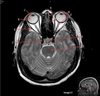

Image weighting and axis

T2 Flair

Sagittal

A

Genu Corpus Callosum

B

Splenium Corpus Callosum

C

Pons

D

Cerebellum